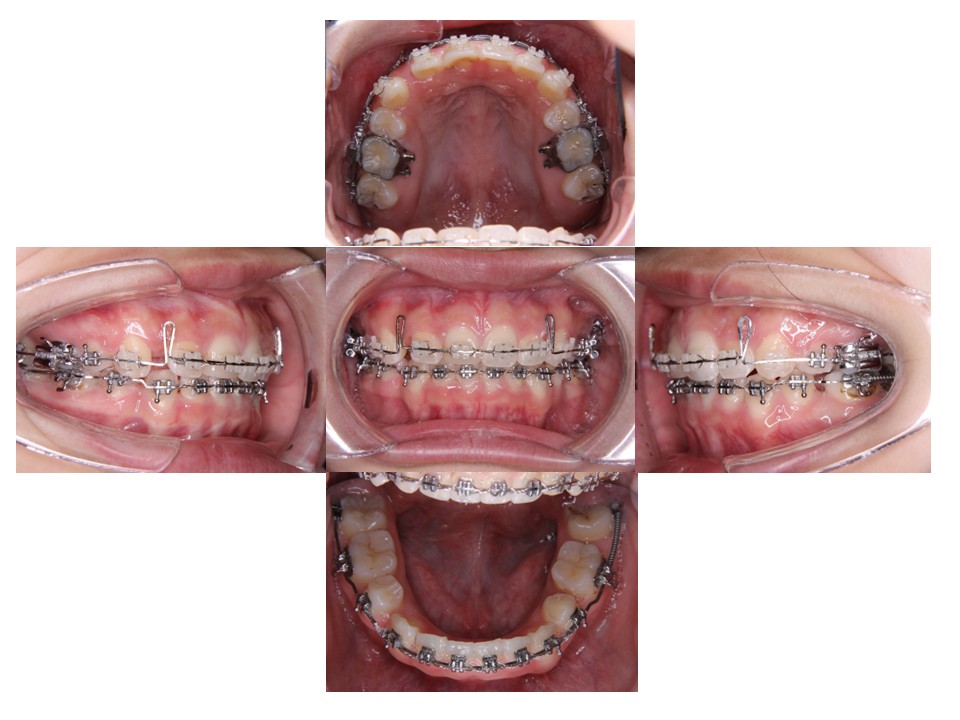

最後の微調整を行っています。

治療終了時